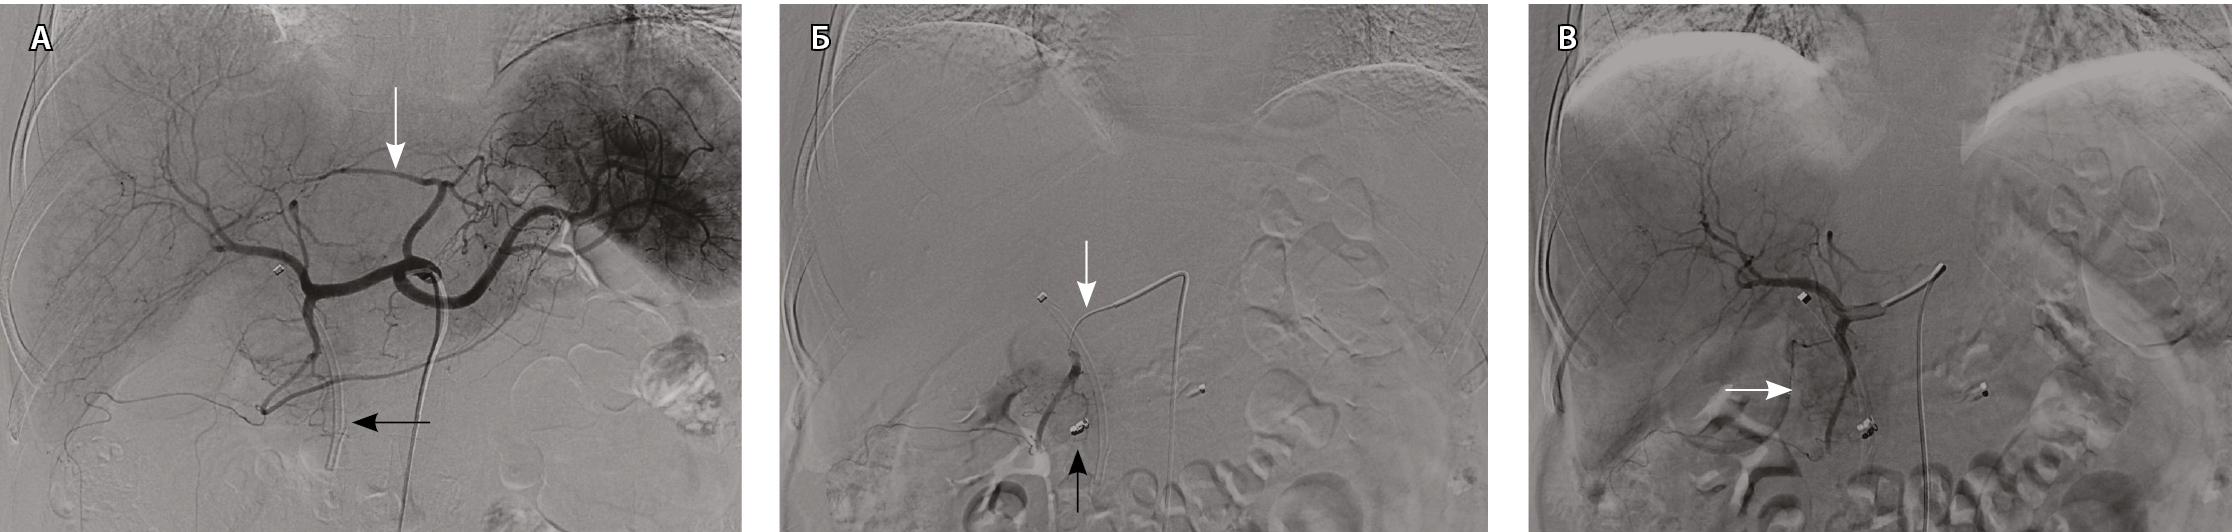

При проведении ангиографии использовали катетеры конфигурации hook или cobra (фирм Cook и Cordis, США или Terumo, Япония) размером 5 F. На ангиограммах из верхней брыжеечной артерии и чревного ствола определяли варианты сосудистой анатомии гепатопанкреатобилиарной зоны, источники кровоснабжения поджелудочной железы, состояние воротной вены по данным возвратной портографии. Затем осуществляли ангиографию общей, собственной печеночных и гастродуоденальной артерий (ГДА) для изучения ангиографических особенностей РПЖ, исключения или подтверждения метастатического поражения печени. Определяли оптимальное место установки катетера в положение, необходимое для проведения лечебного этапа процедуры (рис. 2).

Рис. 2. Ангиограммы пациентки Ш., 67 лет, диагноз: рак головки поджелудочной железы. Механическая желтуха купирована с помощью стентирования. А – при целиакографии отмечается один из вариантов сосудистой анатомии: замещающая левая печеночная артерия отходит от левой желудочной артерии (белая стрелка), правая и средняя – от общей печеночной артерии; пластиковый стент (черная стрелка) определяется в проекции холедоха. Б – катетер cobra 5 F установлен в общую печеночную артерию; коаксиально в правую желудочно-сальниковую артерию проведен микрокатетер 2,7 F, выполнена перераспределительная эмболизация металлической спиралью (черная стрелка); следующим этапом выполнена химиоэмболизация ветвей гастродуоденальной артерии, кровоснабжающих опухоль (белая стрелка). В – во время контрольной ангиографии из общей печеночной артерии отмечается накопление масляного препарата в опухоли (белая стрелка)